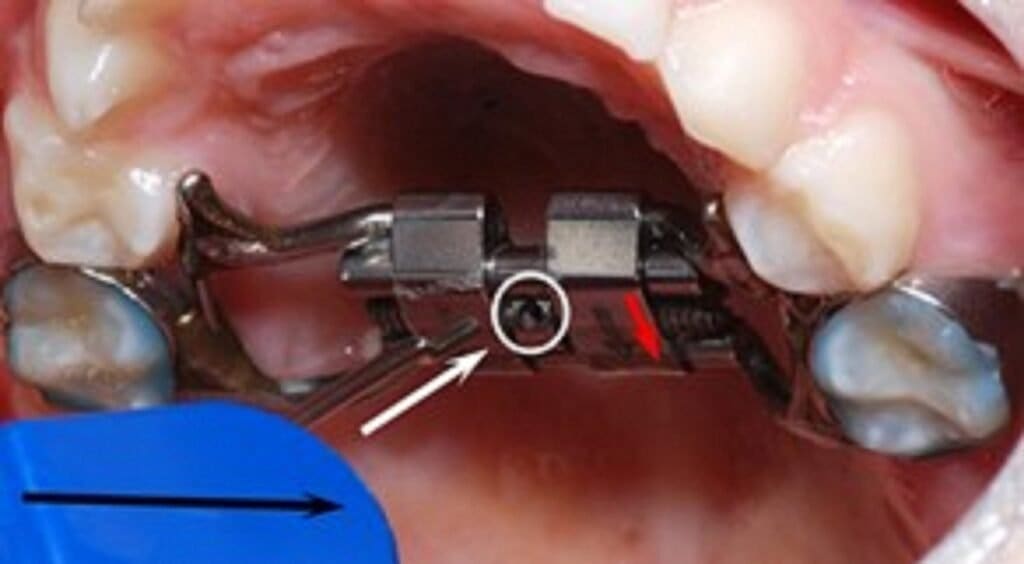

Temporary anchorage devices (TADs) can be used as skeletal anchorage in combination with the expansion appliance. Thus, miniscrews can be inserted on each side of the median palatal suture to replace teeth as anchorage units (Ludwig et al., 2013).

Also called MICROIMPLANT-assisted R.M.E technique (MARPE).

Miniscrews are employed onto the maxillary expanders that recruits palatal and nasal cortices. This provides anchorage that facilitates opening of mid-palatal suture and helps to overcome resistance from circum-maxillary sutures.

Paramedian area 3mm lateral to the suture in 1st premolar region is considered the most appropriate site for placement of miniscrews, anterior screws are placed in rugae.

Skeletal anchorage should permit orthopaedic change without adverse dental changes by applying force directly to the maxillary bone.

With a jackscrew attached to skeletal anchors, rapid disruption of the suture would be a disadvantage, so slow (<2 mm per week) rather than rapid expansion is indicated.